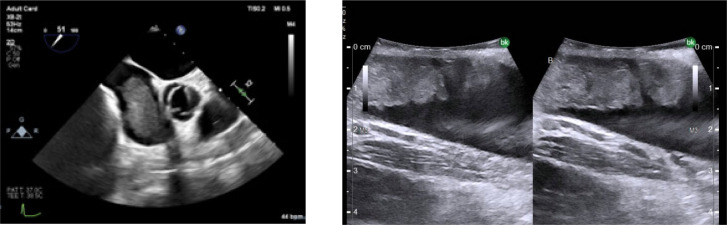

Intraoperative tumor thrombus embolization is a potentially lethal complication during inferior vena cava (IVC) thrombectomy for renal cell carcinoma (RCC). Intraoperative embolization is uncommonly encountered because IVC thrombectomy surgical technique is focused on avoiding this complication. Nonetheless, early recognition of embolization is essential so that emergent management can be instituted. When available, cardiopulmonary bypass (CPB) and embolectomy should be considered the gold standard for the management of intraoperative embolization. Several novel endovascular techniques are also available for selective use. We present the case of a 71-year-old female with a right renal mass and level II (retrohepatic) IVC tumor thrombus. During cytoreductive nephrectomy and IVC thrombectomy, tumor embolization was diagnosed during a period of hypotension based on transesophageal echocardiographic finding of new thrombus within the right atrium. This prompted sternotomy, CPB, and pulmonary artery embolectomy. The patient survived this embolization event and has a complete response to systemic therapy 9 months postoperatively. This case serves as the framework for a discussion on management considerations surrounding intraoperative embolization during IVC thrombectomy.

Abstract Image